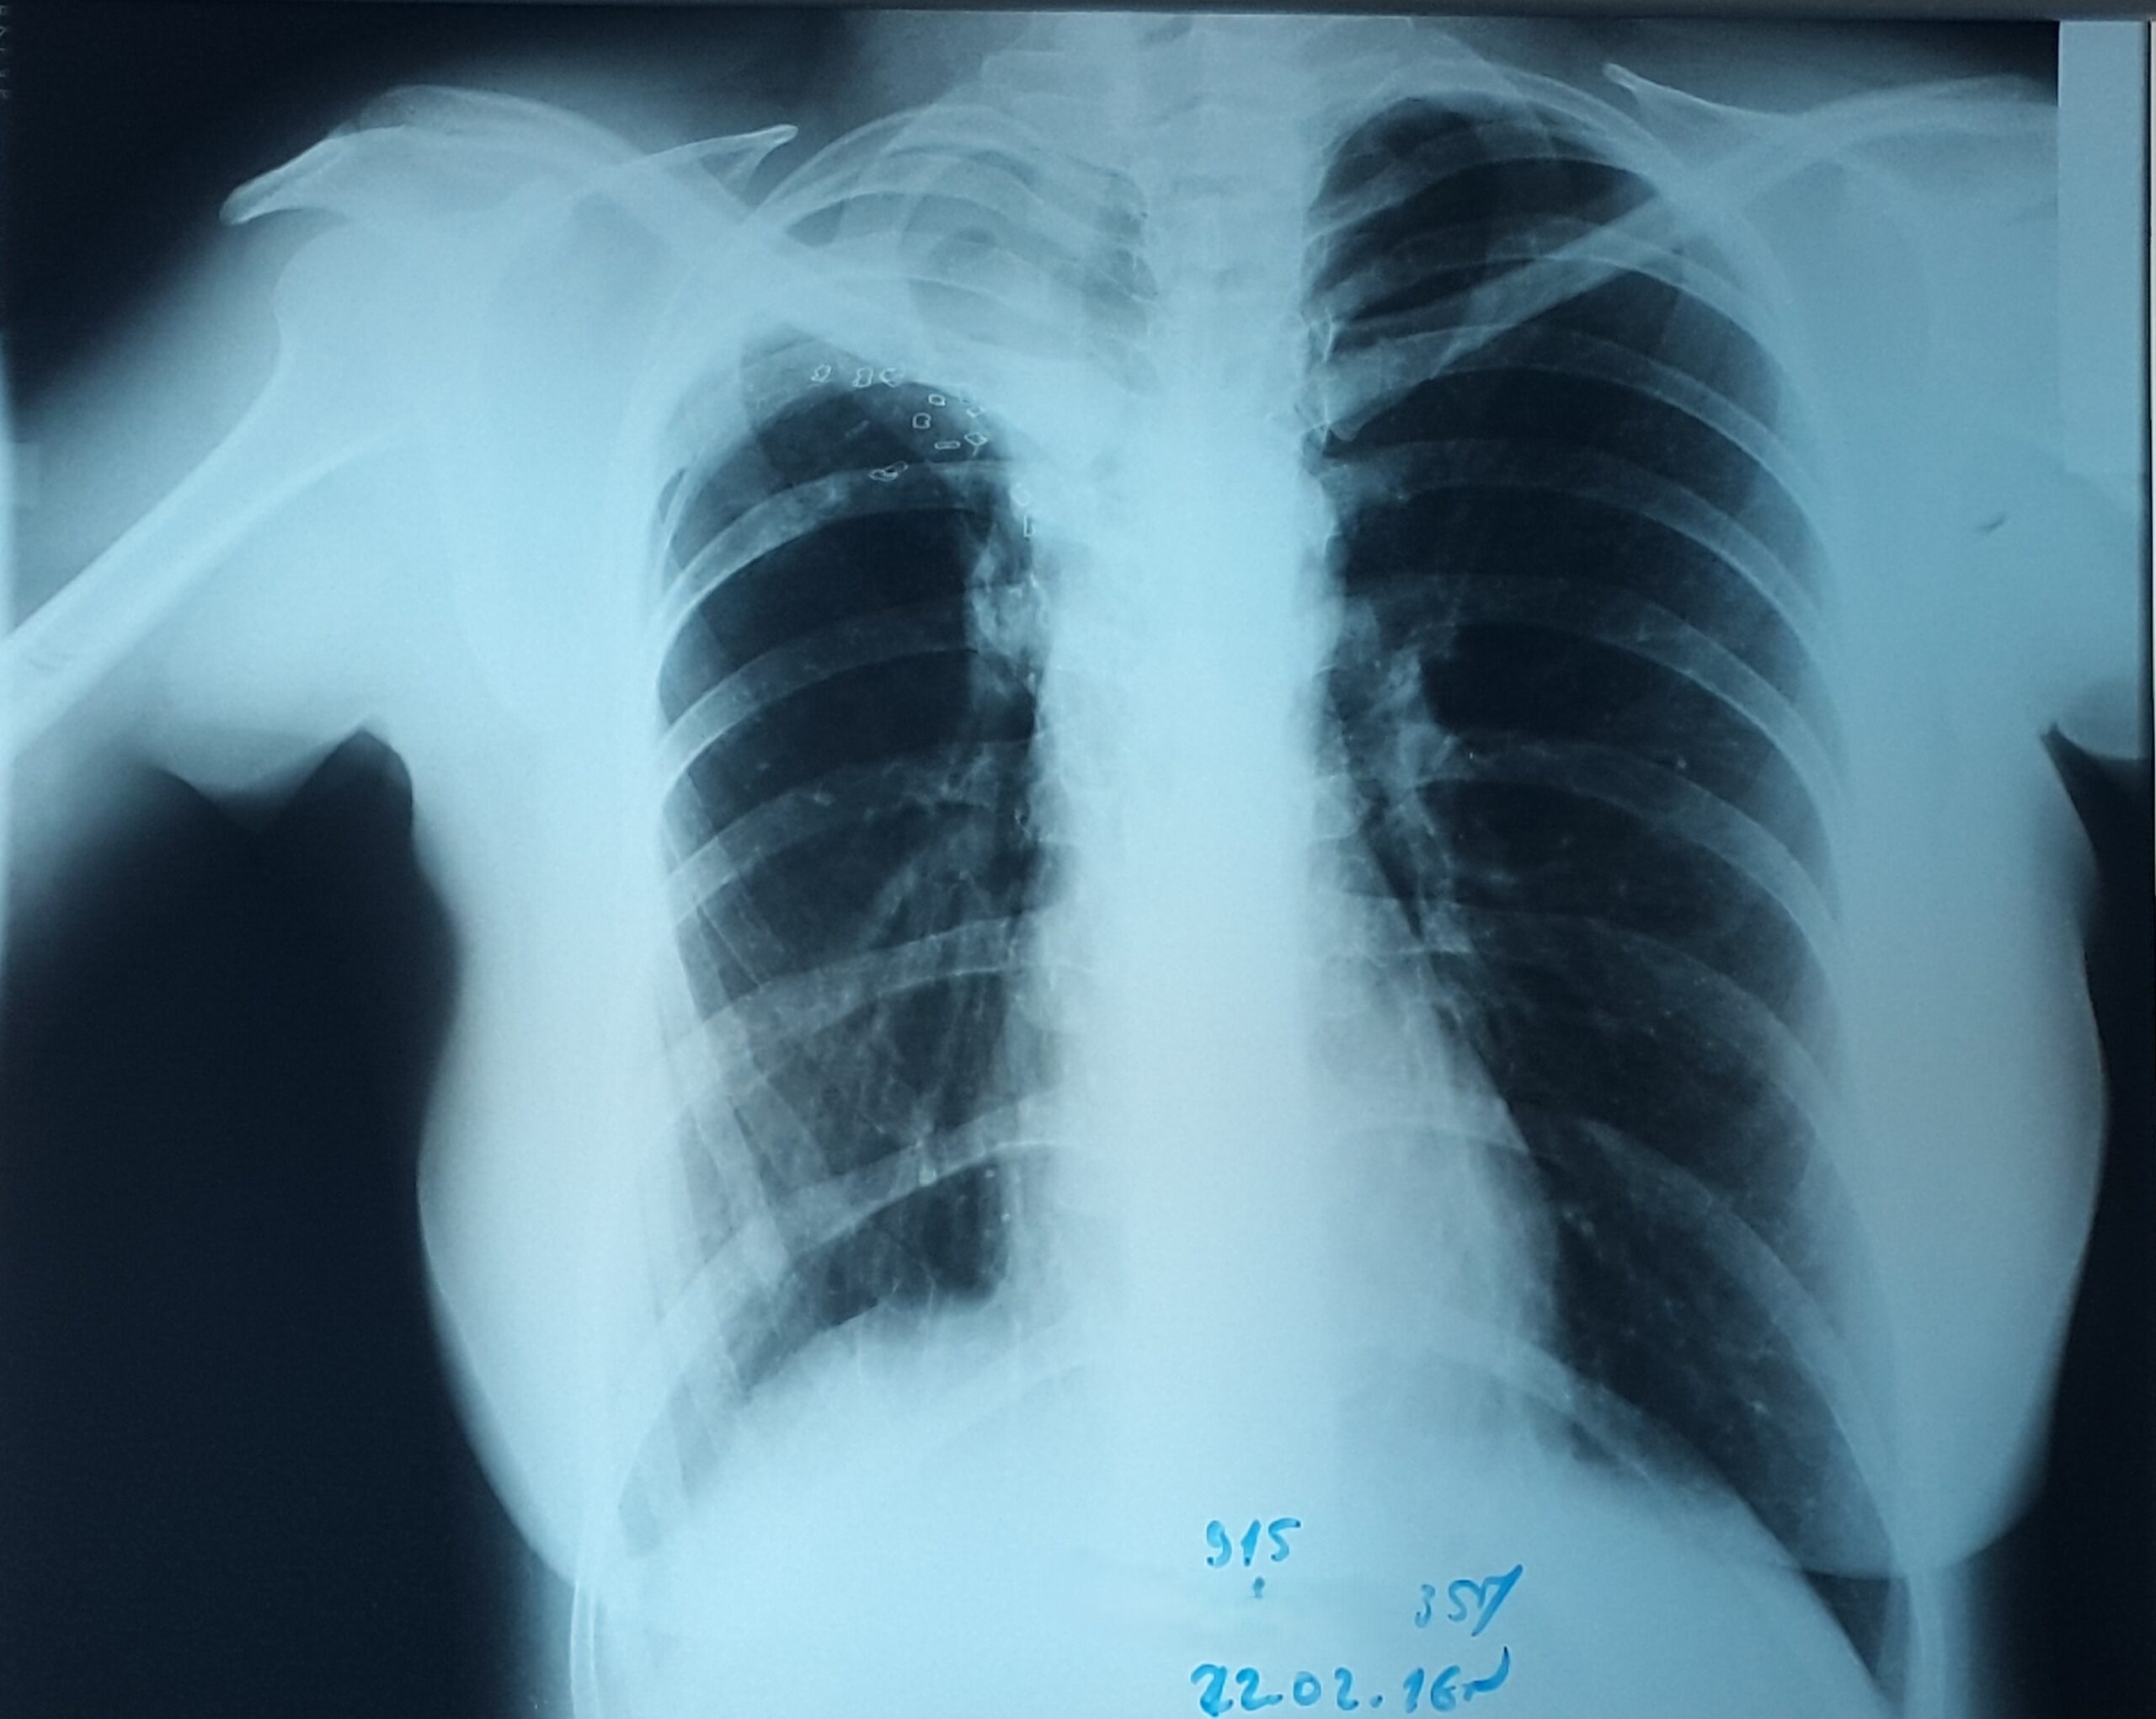

პაციენტი 37 წლის ქალი. 1997 წ-ს გაკეთებული აქვს მარჯვენა ზედა წილის რეზექცია ფილტვის ტუბერკულოზის გამო. წლების განმავლობაში აქვს გამწვავებები, რაც გამოიხატება მაღალი ცხელებით, ხველით, დიდი რაოდენობით სისხლნარევი, მძაფრი სუნის მქონე ნახველის გამოყოფით. რენტგენოლოგიურად ინახა დიდი ზომის ღრუ მარჯვენა ფილტვის ზედა ველში. ბრონქოსკოპიით ინახა დიდი ზომის მარჯვენა ზ/წილოვანი ბრონქის ტაკვის ფისტულა. ტაკვის სიგრძე იძლეოდა ბლოკატორის ჩადგმის შესაძლებლობას. რიგიდული ბრონქოსკოპით მარჯვენა ზ/წილოვან ბრონქში ჩაიდგა MEDLUNG-ის ბლოკატორი N13. რამოდენიმე საათში საჭირო გახდა ბლოკატორის გამოცვლა ნაკლებ (N12) ზომაზე განვითარებული მარჯვენა ქვედა წილის ატელექტაზის გამო. მანიპულაციის შემდეგ პაციენტს შეუწყდა სისხლნარევი და ჩირქოვანი სეკრეტი. 10 თვის შემდეგ საკონტროლო გამოკვლევით ღრუს ადგილას დაფიქსირდა ფიბროთორაქსი. უახლოეს მომავალში, გულმკერდის კტ კვლევის შემდეგ, იგეგმება ბლოკატორის ამოღება.